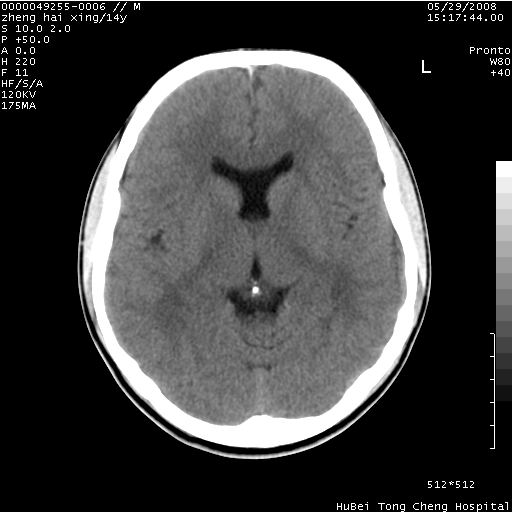

颅脑ct轴位平扫(层厚、层距均为10mm),图像如下:

双侧侧脑室之间无透明隔,双侧额角前方变扁,交角变钝。支持透明隔缺如!

调一下窗寛窗位,或者透明隔太薄,容积效应而显示不好。